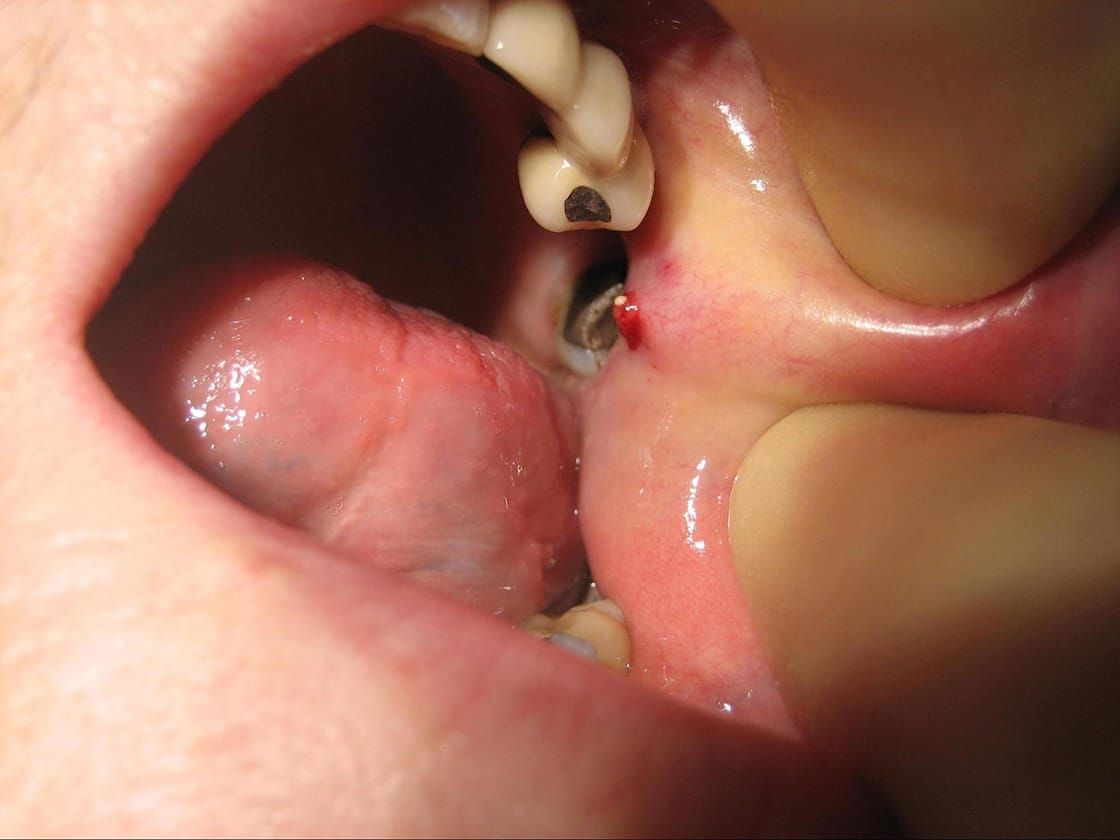

The management of these conditions varies according to your diagnosis. Small stones can be easily removed via sialendoscopy.

Sialendoscopy

This is a minimally invasive procedure similar to key-hole surgery, where a very small camera is inserted into the ducts through their natural openings in the mouth. The benefits of sialendoscopy are thus less swelling, pain, bleeding, infection and a faster recovery. Its completed in one visit as a day case procedure.

Before sialendoscopy was available, stones/narrowings in the submandibular duct would necessitate the need to remove the entire gland – with potential complications such as facial weakness, tongue numbness and weakness. Now we can reduce this risk by minimally invasive procedures such as sialendoscopy. However, there are still certain cases that warrant removal of the whole gland, which is carried out under a General Anaesthetic.

See below for images of stone removal from left parotid duct.